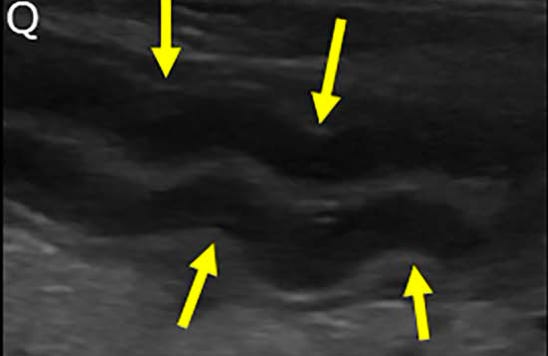

Corrugación intestinal: